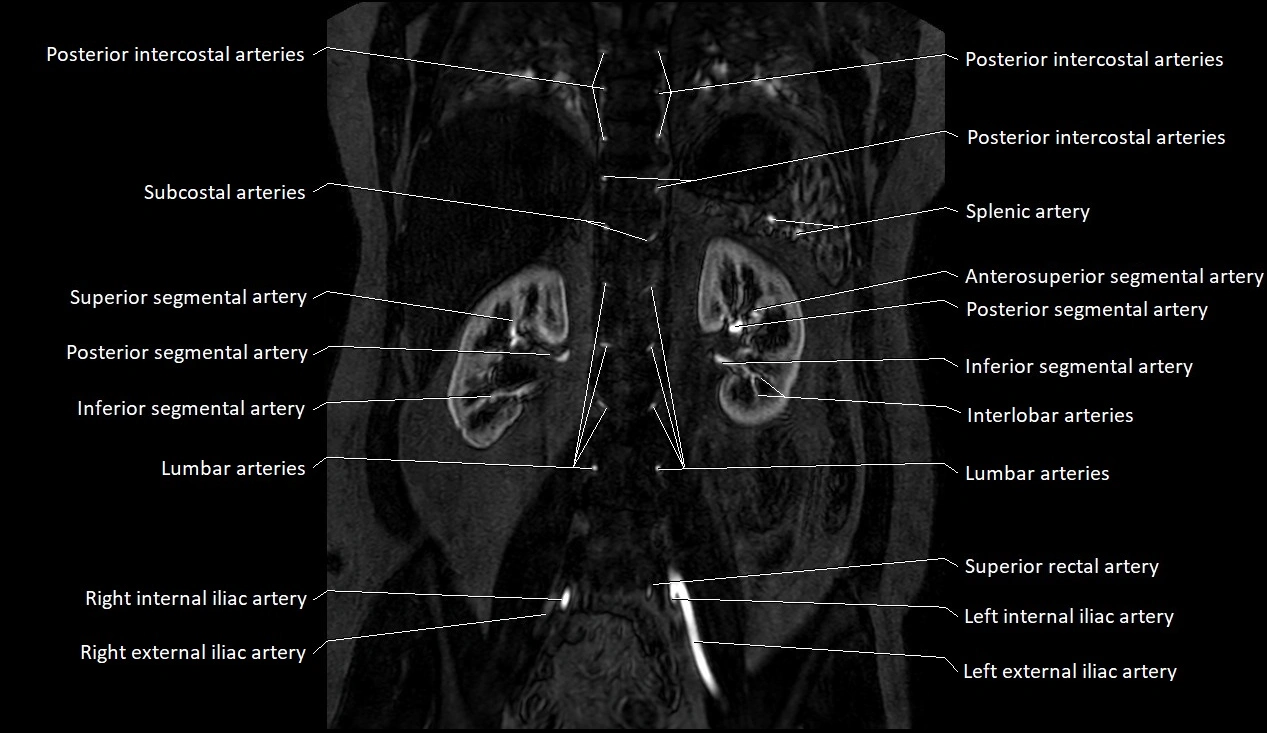

MRI images

image